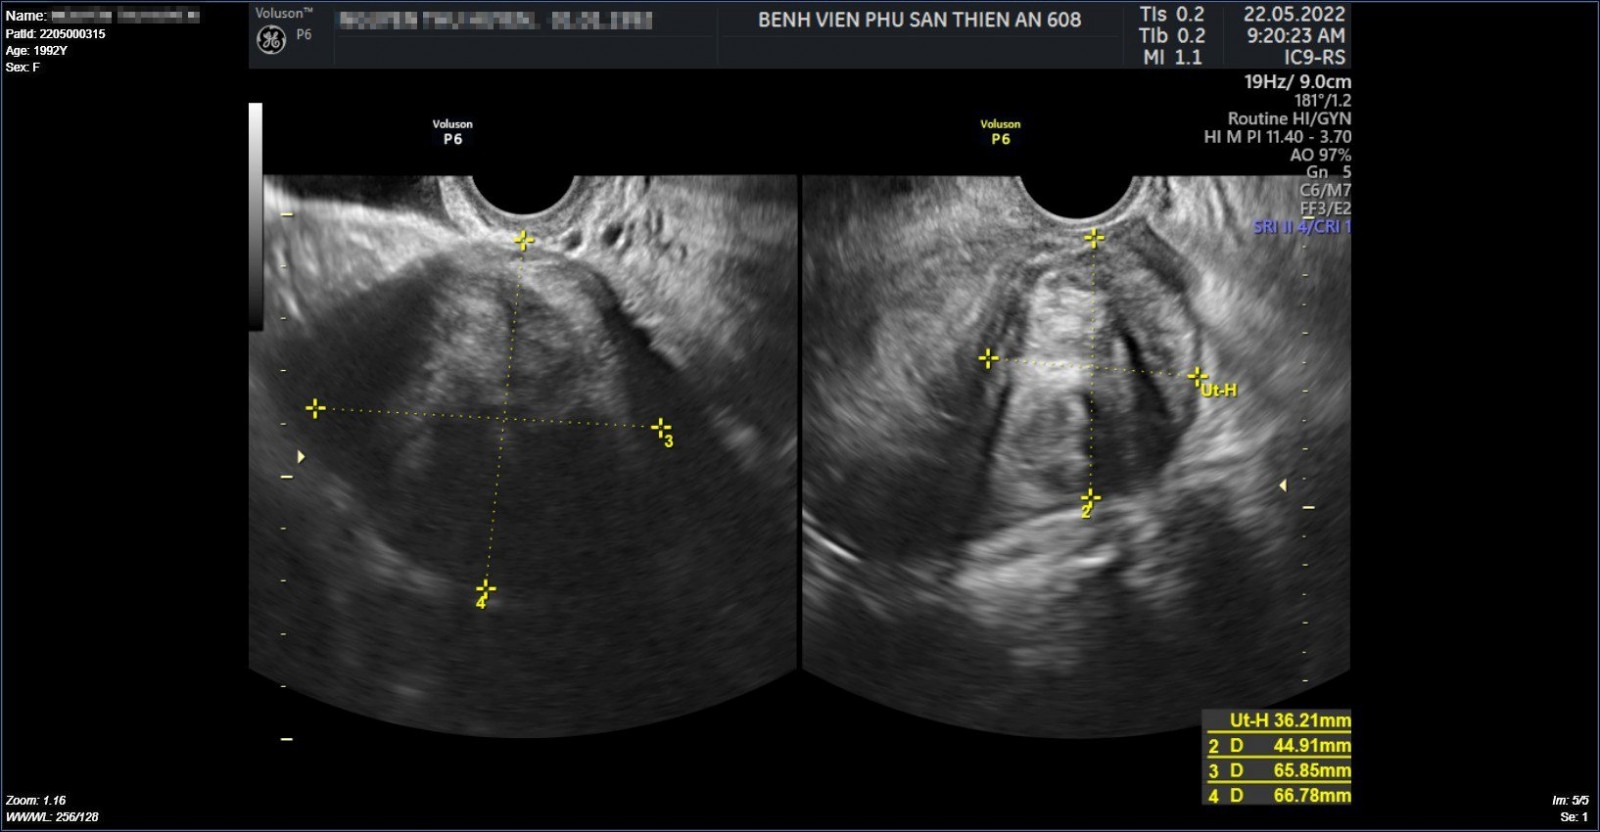

Hình ảnh tử cung có khối u xơ tử cung lớn của chị H. trước khi phẫu thuật

Qua thăm khám, GS Nguyễn Viết Tiến đã xác định khối u của chị hoàn toàn có thể được xử lý, bóc tách bằng phẫu thuật nội soi. Mổ nội soi là phương pháp hiện đại xâm lấn tối thiểu, thẩm mỹ cao và thời gian phục hồi nhanh, nhưng đối với những trường hợp khối u lớn như của chị H. muốn mổ được cần phải phẫu thuật viên dày dặn kinh nghiệm cũng như trình độ chuyên môn cao.